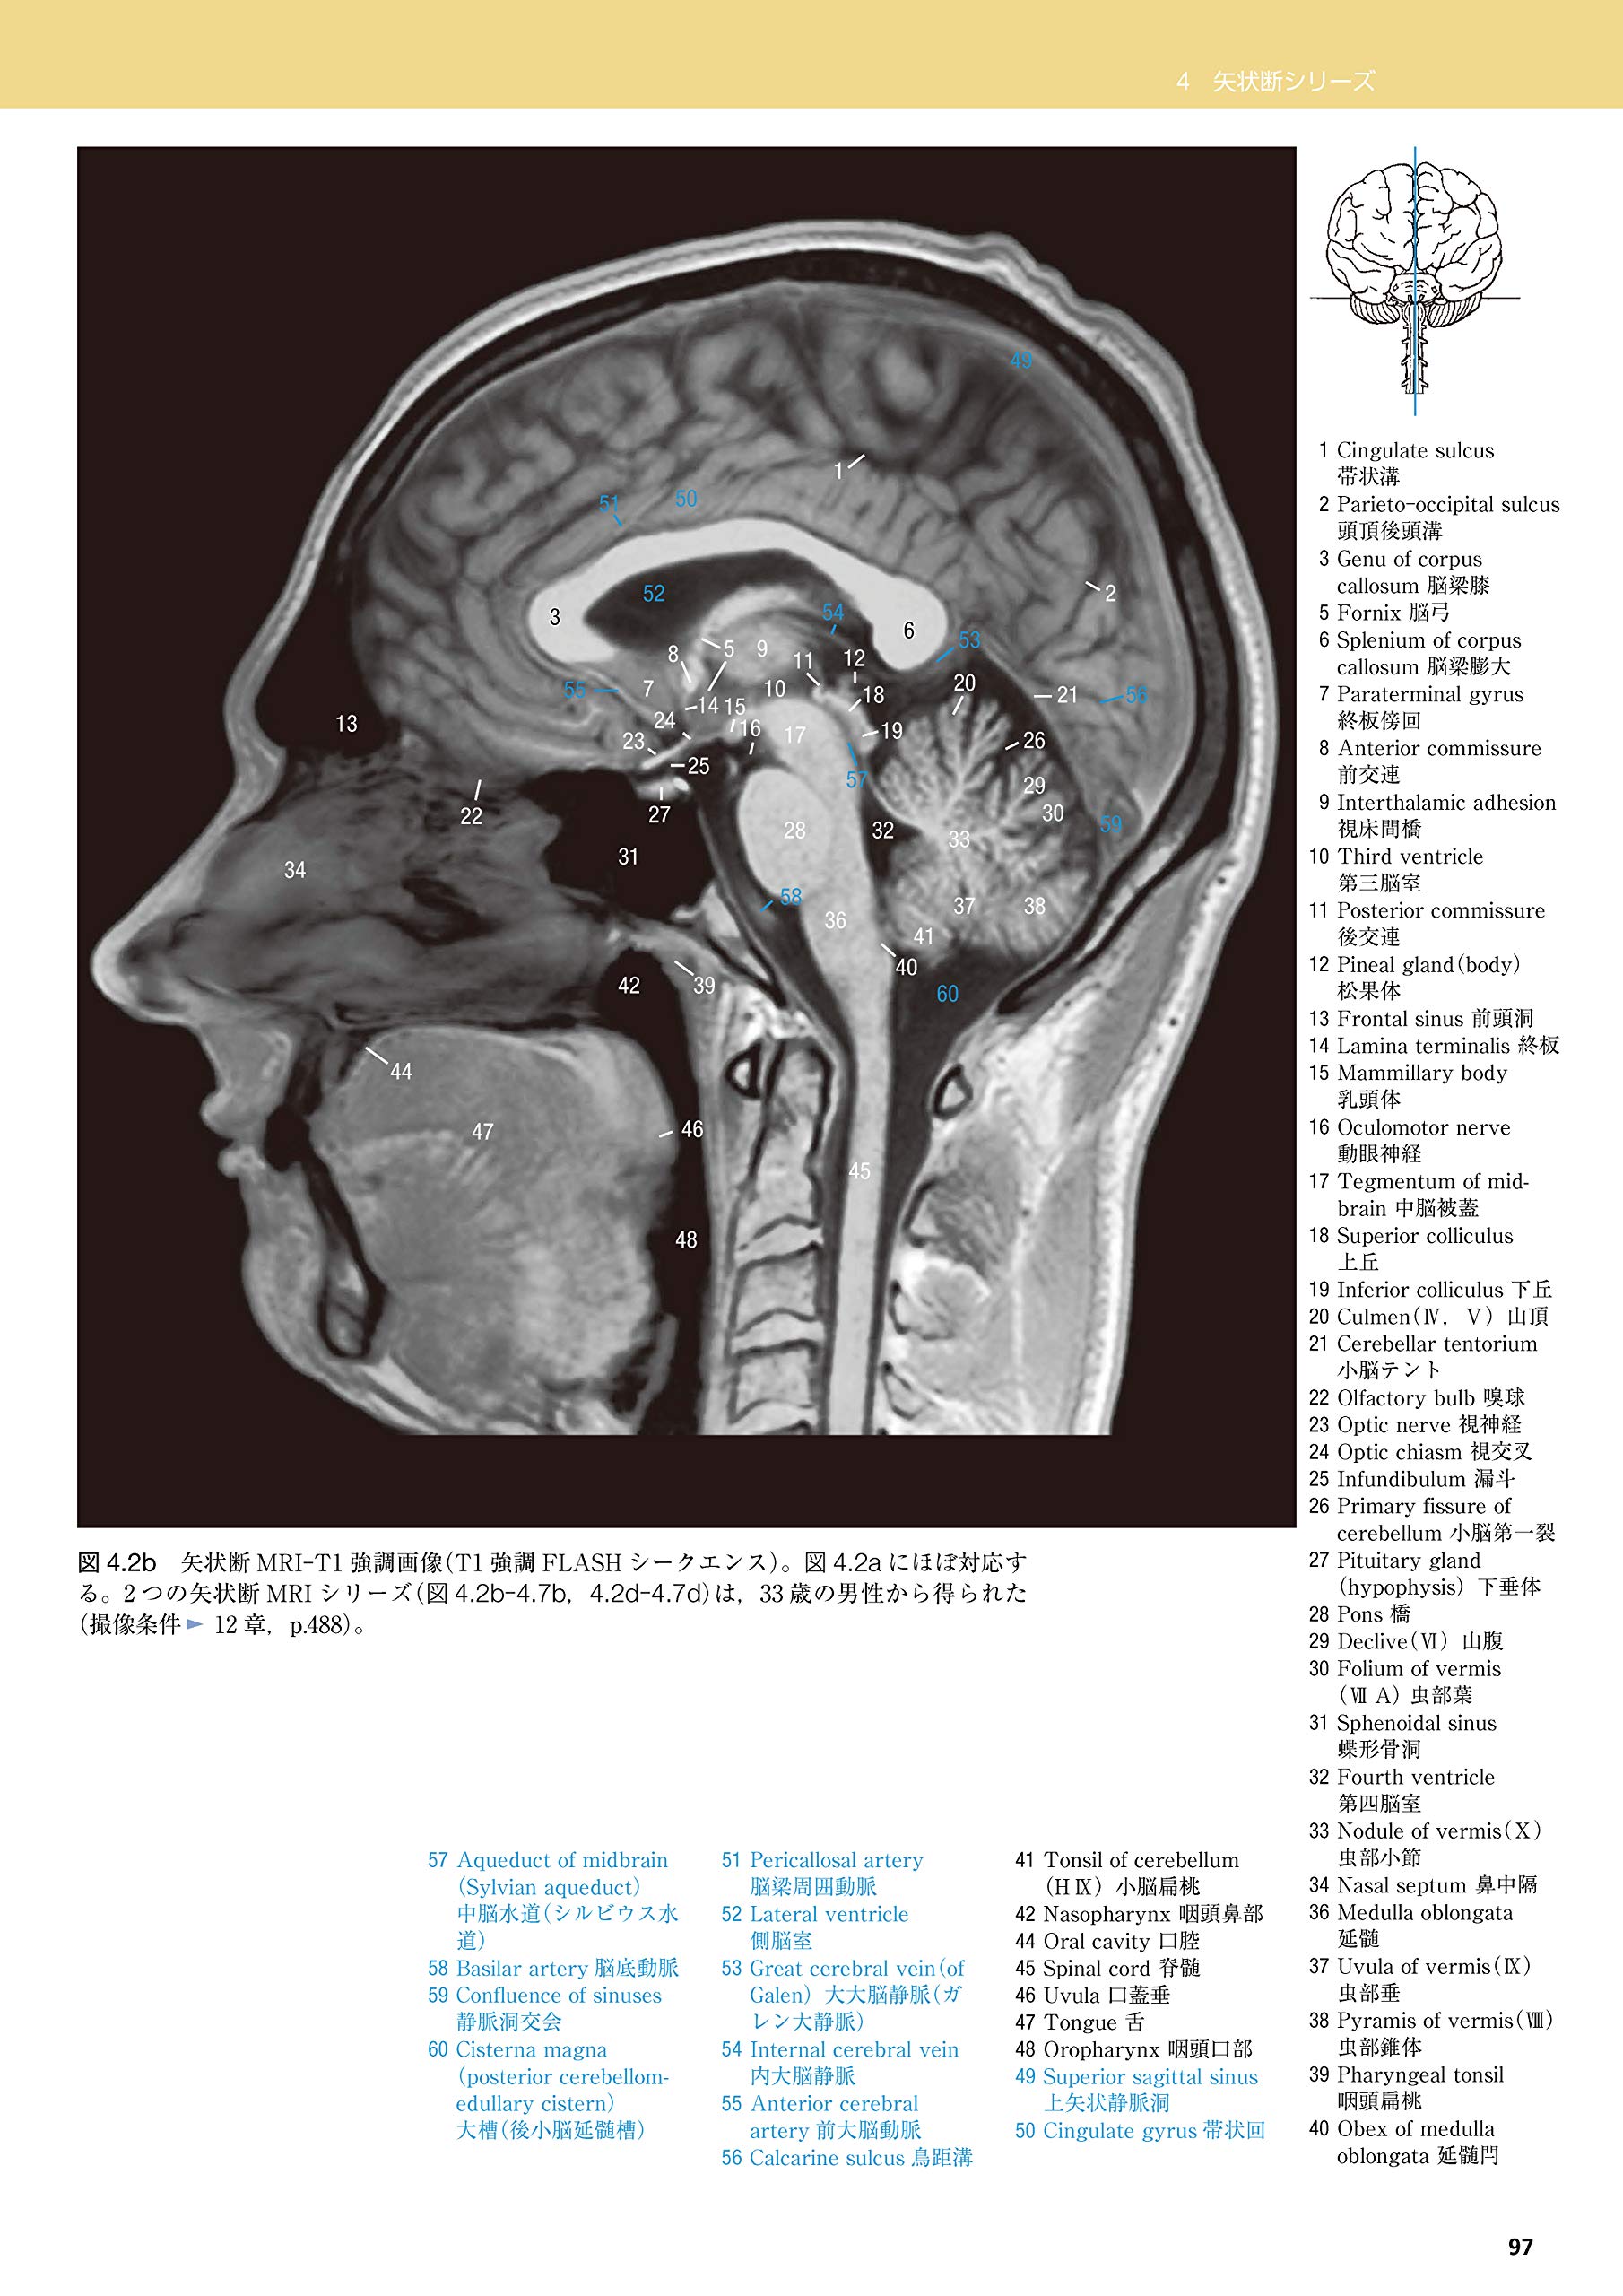

脳断面図 正中矢状 mサイズ Laiman Stockweb メディカルイラスト素材のダウンロード販売

脳 正中断面 Laiman Stockweb メディカルイラスト素材のダウンロード販売